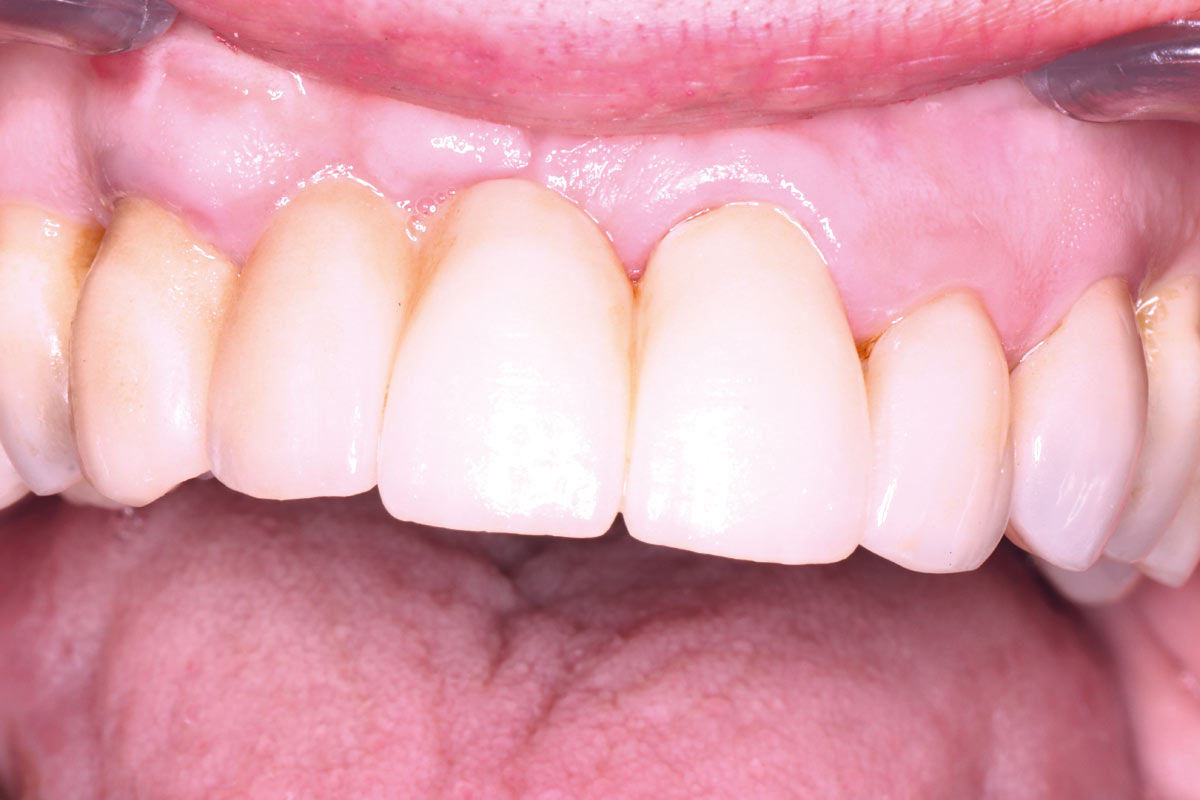

08/10 - 22 months follow-upMaxillary bone reconstruction in the anterior area with cerabone® and Jason® membrane - Dr. P.-Y. Gegout & Prof. O. Huck

10/10 - Post-operative x-ray after 22 months; a bridge solution was selected as the adjacent teeth required also crown replacementMaxillary bone reconstruction in the anterior area with cerabone® and Jason® membrane - Dr. P.-Y. Gegout & Prof. O. Huck